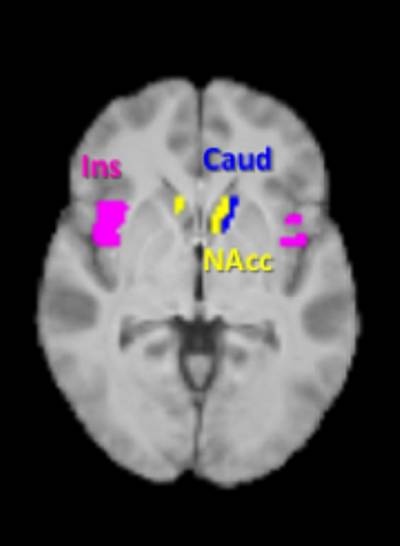

Zonas del cerebro asociadas con el anhelo de comida. Las áreas marcadas en azul y amarillo, llamadas caudado y núcleo accumbens, mostraron una menor activación ante alimentos ricos en calorías cuando los voluntarios tomaron el suplemento alimenticio. (Foto: Tony Goldstone, Imperial College London)

El equipo de Gary Frost, del Imperial College en Londres, encontró que cuando los voluntarios habían bebido el batido de leche que contenía el éster de propionato-inulina, tenían, al mirar imágenes de comida, menos actividad en áreas de su cerebro vinculadas a la recompensa, pero solo cuando las imágenes que miraban eran de alimentos ricos en calorías. Estas áreas, llamadas núcleo accumbens y caudado, situadas en el centro del cerebro, han sido previamente relacionadas con el deseo de comida.